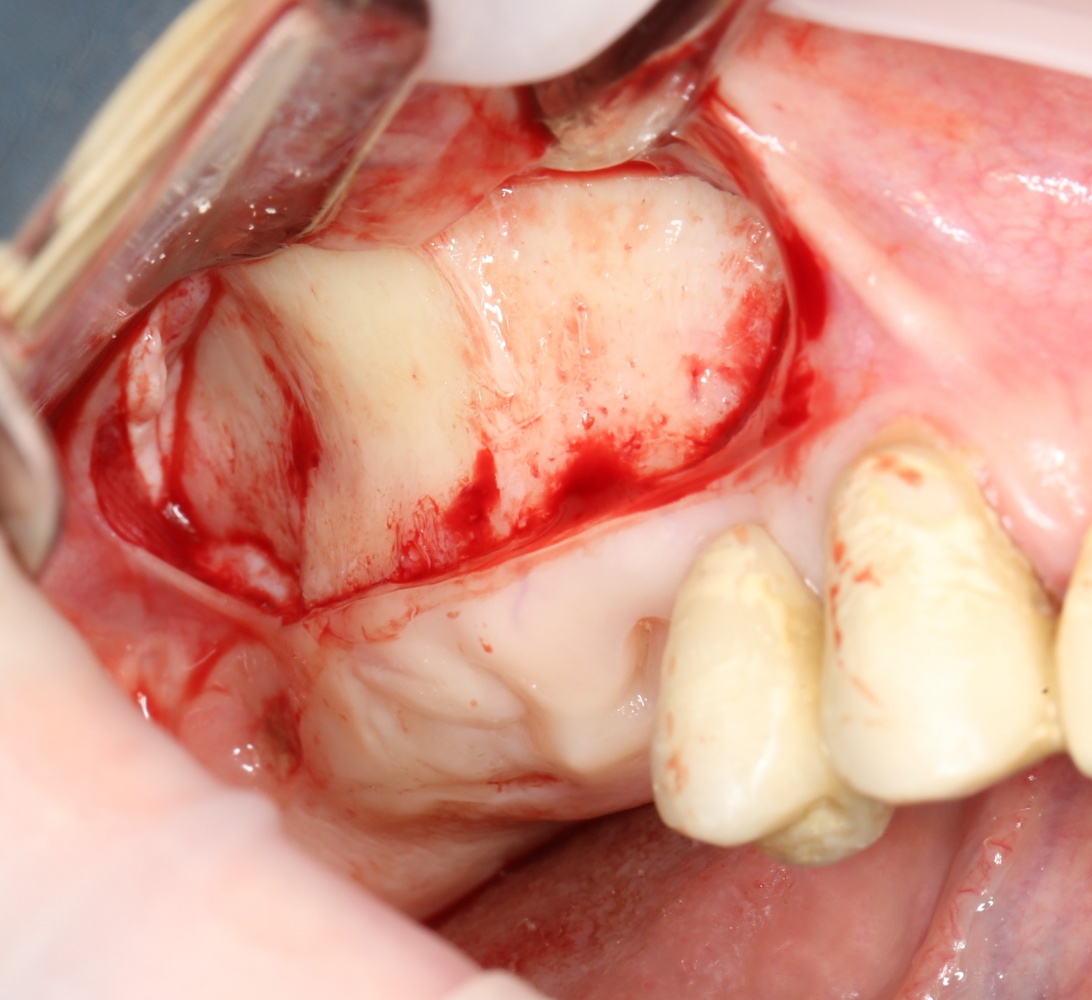

Для получения костного блока, мы открываем донорскую зону, наружную косую линию нижней челюсти.

Получение костного аутотрансплантата.

Здесь потребуется пародонтологический зонд с миллиметровой разметкой или какой-то другой измерительный прибор (операционная линейка). Ранее по КЛКТ я измерил костный дефект, теперь нужно нанести границы будущего костного блока на донорскую зону.

Ремарка: некоторые доктора предлагают делать хирургические шаблоны или выкройки специально для точного забора костного блока. На мой взгляд, это чрезмерное усложнение - во-первых, использование подобных шаблонов или выкроек требует увеличения площади раны, во-вторых, это увеличивает время и стоимость лечения, в-третьих, на этом этапе не требуется высокая точность, поскольку блок всё равно потребует адаптации.

Иными словами, важна не точность, а быстрый, аккуратный и, что главное, малотравматичный забор аутотрансплантата.

Для получения костного блока мы использовали ультразвуковую пьезохирургическую систему. Это самый удобный и безопасный инструмент для проведения подобных манипуляций. С помощью него мы сформировали и выделили костный блок. Он должен отделяться легким движением остеотома или элеватора. Как это сделать правильно — читай здесь>>